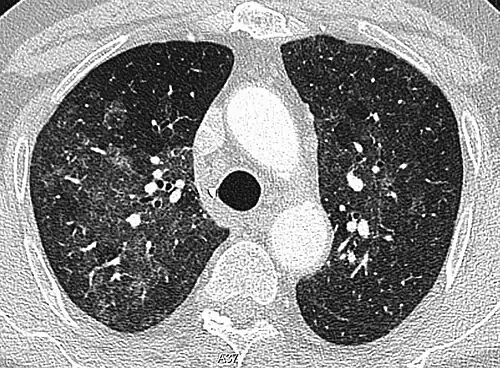

High-resolution CT image showing ground-glass opacities in the periphery of both lungs in a patient with COVID-19 (red arrows). The adjacent normal lung tissue with lower attenuation appears as darker areas.

Ground-glass opacity is among the most common imaging findings in patients with confirmed COVID-19.[16][17] One systematic review found that among patients with COVID-19 and abnormal lung findings on CT, greater than 80% had GGOs, with greater than 50% having mixed GGOs and consolidation.[16] GGOs with mixed consolidation has most often been found in elderly populations.[18] Several studies have described a pattern among initial, intermediate, and hospital discharge imaging findings in the disease course of COVID-19. Most commonly, initial CT imaging reveals bilateral GGOs at the periphery of the lungs. During initial stages, this is most often found in the lower lobes, although involvement of the upper lobes and right middle lobe has also been reported early in the disease course.[16][18] This is in contrast to the two similar coronaviruses, SARS and MERS, which more commonly involve only one lung on initial imaging.[19][20] As the COVID-19 infection progresses, GGOs typically become more diffuse and often progress to consolidation.[11][18] This is sometimes accompanied by the development of a crazy paving pattern and interlobular septal thickening.[18] In many cases the most severe pulmonary CT abnormalities occurred within 2 weeks after symptoms began.[17] At this point, many individuals begin showing resolution of consolidation and GGOs as symptoms improve. However, some patients have worsening symptoms and imaging findings, with further increase in septal thickening, GGOs, and consolidation. These patients may develop lung "white-out" with progression to acute respiratory distress syndrome (ARDS) requiring treatment escalation.[17][21]

Preliminary reports have shown many patients have residual GGOs at time of discharge from the hospital. Due to the novelty of COVID-19, large studies investigating the long-term pulmonary CT changes have yet to be completed. However, long-term pulmonary changes have been seen in patients after recovery from SARS and MERS, suggesting the possibility of similar long-term complications in patients who have recovered from acute COVID-19 infection.[22]